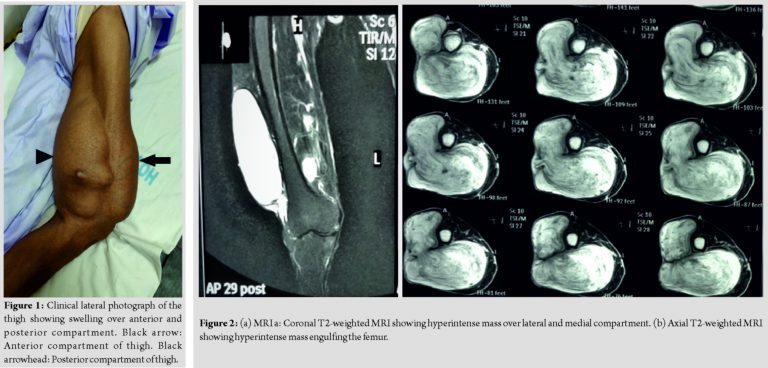

The patient was a 70-year-old male who presented to the orthopedic outpatient clinic with a slowly progressive swelling around his right thigh over the past 10 years. The patient had observed the swelling grow to its present size which was relatively painless in the past, but painful for the past 6 months, thereby causing difficulty in his activities of daily living. The pain was present even at rest and radiated to the right leg. On clinical examination, there was a smooth, lobulated, painless, and firm swelling covering the back of the thigh extending anteriorly, medially as well as laterally. On the posterior surface, it was approximately 25 × 10 cm, with anterior lobulation approximately 15 × 5 cm (Fig. 1).

Medial as well lateral extensions were diffuse. The plain radiograph of the limb showed no bony involvement. Magnetic resonance imaging (MRI) revealed a well circumscribed encapsulated lobulated soft tissue mass measuring 25 × 15.5 × 10cm in the lower half of the thigh appearing heterogeneously hyperintense on T2 STIR sequence with a T2 hypointense rim and a hypointense T1, giving a whorled appearance. The mass was located mainly in the posterior compartment (just deep to superficial fascia and intermuscular planes), extending into anterior compartment along the lateral aspect of thigh caudally extending up to levels of the femoral condyles (Fig. 2a and b). No obvious invasion of the neurovascular bundle was seen; however, it was displaced medially lying in close proximity to the swelling. Tumor workup such as computed tomography of the chest and ultrasonography of the abdomen was normal. Routine blood investigations revealed mild anemia and ESR of 24mm/h. A biopsy was performed which was suggestive of a benign myxoid neoplasm. Having obtained the pathological diagnosis, surgical excision was planned for which due consent was obtained. Excision was performed by a single curvilinear incision over the posterior thigh, curving from superomedial to inferolateral direction, incorporating the biopsy site into it. The tumor was identified as swelling with a shiny white capsule, with rubbery consistency, lying in a subcutaneous plane extending to the intermuscular plane. The tumor was excised en-bloc without any spillage measuring 23 × 18 × 6 (Fig. 3a). The post-operative period was uneventful with no neurovascular deficit. Histopathology report showed moderately cellular growth with an abundant myxoid matrix containing oval to spindle cells with monomorphic nuclei and bland chromatin. No nuclear atypia or increased mitosis was seen (Fig. 3b). Immunohistochemistry markers were done which revealed accentuation of blood vessels on SMA, which was negative in tumor cells, few cells positive for S-100 and Ki-67 was <1% indicative of low proliferative index. Histopathological diagnosis was consistent with intramuscular myxoma. At the final follow-up of 26 months, the patient was asymptomatic and showed no signs of recurrence.